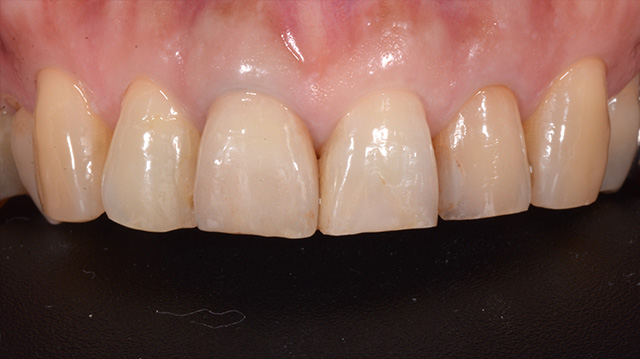

| 年代・性別 | 40代 男性 |

|---|---|

| 主訴 | 前歯の色が気になる |

| 治療回数 | 3回 |

| 治療期間 | 約1ヶ月 |

| 費用 | 仮歯 5,500円 ジルコニアクラウン 176,000円 |